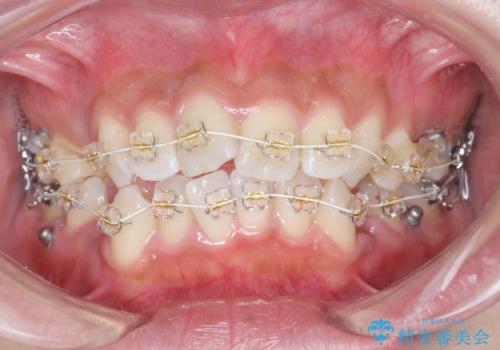

ガタつきと口元の改善 抜歯を伴うワイヤー矯正

- 唇の閉じづらさと、前歯のがたつきの改善を希望され来院されました。

抜歯を行わなくてもなんとか並べられる歯並びですが、唇の閉じづらさをしっかりと改善するため抜歯を伴うマルチブラケット矯正を行うこととしました。

前歯をしっかりと後方に引いたことで、唇は閉じやすくなり、仕上がりに満足いただくことができました。